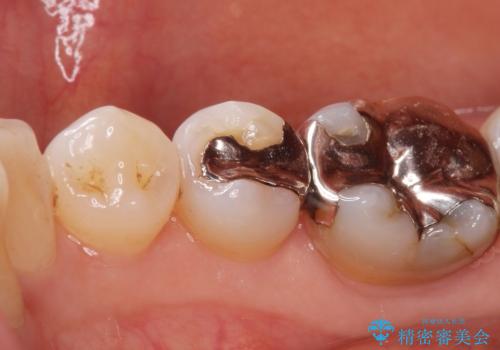

口を開けると銀歯が見えるのが嫌だ。

- 口を開けると銀歯が見えるのが嫌とのことで来院。

銀歯を外し、拡大鏡下で虫歯を全て取り除き、白い詰め物(e-maxインレー)にて治療することになりました。

まずは一つ治療したいとの事だったので手前の小臼歯から行いました。